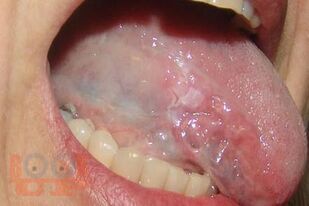

Методические рекомендации разработаны на основании законодательных и научных литературных данных. В рекомендациях изложены общие сведения об онкологических заболеваниях челюстно-лицевой области, алгоритмы и способы диагностики, профилактики злокачественных новообразований, особенности их клиники при различных локализациях на лице и в полости рта. Представлена тактика врача при подозрении на онкозаболевание, указаны предраковые состояния, которые требуют особого внимания специалистов. Методические рекомендации предназначены для организаторов здравоохранения, врачей первичного звена, врачей специалистов, студентов стоматологических факультетов, интернов, врачей-ординаторов.